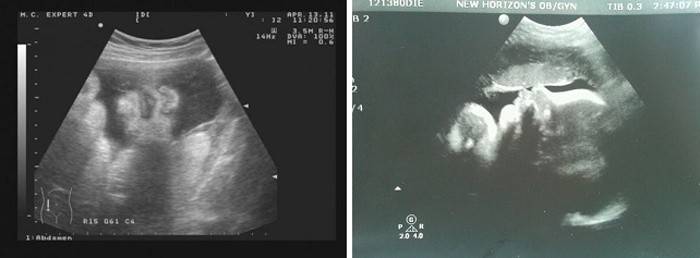

Ultrazvukové vyšetrenie (Uzi)

Všetky plánované ultrazvuky už boli ukončené av tomto období je štúdia predpísaná na ďalšie objasnenie prezentácie a výskumu niektorých ukazovateľov. Lekár pomocou senzora a dopplerometrie vyhodnotí parametre ultrazvuku - polohu plodu a stav pupočnej šnúry a placenty, množstvo plodovej vody a ich stav, prietok krvi plodu a stupeň zrelosti placenty. Pomôže to lekárovi rozhodnúť o liečbe pôrodu - bude to prirodzená časť alebo cisársky rez.

Ultrazvuk určuje odhadovaný dátum narodenia, odhadovanú hmotnosť, rast plodu, zrelosť placenty a neprítomnosť patologických inklúzií. Lekár tiež podrobne preskúma stav vnútorných orgánov plodu. Ak je to potrebné, rodičia vedú aj 3D ultrazvuk, v ktorom skúmajú tvár dieťaťa a všetky jeho orgány a systémy, fotografujú.